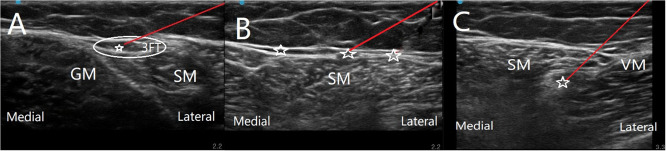

Purpose: Minimally invasive intervention therapy anterior cutaneous branch of the femoral nerve for refractory neuropathic pain in the inner thigh area typically requires punctures at multiple sites to target the three nerves of the obturator nerve cutaneous branch, anterior cutaneous branch of the femoral nerve, and infrapatellar branch of the saphenous nerve. Clinical practice has demonstrated that the innovative "three-in-one" technique allows for simultaneous targeting of the three cutaneous nerves from a single entry point, effectively treating inner thigh pain. Moreover, this approach can also be used for local anaesthesia in shallow surgical procedures in the inner thigh area. We hope to promote this puncture technique among pain physicians.

Patients and methods: Clinical data of 8 patients with localized pain in the inner thigh from the Pain Department of Taihe Hospital, Shiyan City, Hubei Medical College, from April 2023 to September 2024 were collected. All the patients experienced pain in the cutaneous branch of the obturator nerve, the anterior branch of medial femoral cutaneous nerve, and the infrapatellar branch of the saphenous nerve. The "three-in-one" approach was used for nerve block and radiofrequency puncture.